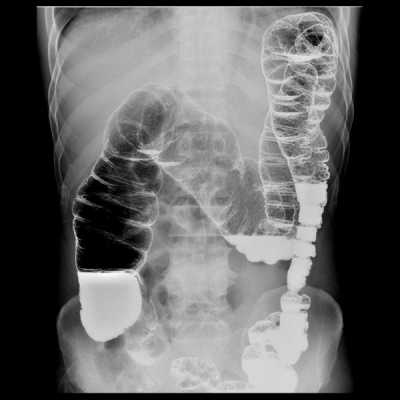

2.4. Ирригоскопия

Рентген органов пищеварительной системы (пищевод, желудок, толстая кишка)

Показания к рентгенологическому исследованию органов пищеварительной системы:

- Подготовка к плановой операции

- Выявление органических заболеваний (опухолей) пищевода, желудка,12 пк, толстой кишки, оценка объема поражения.

- Выявление инородных тела пищевода, желудка, тонкого и толстого кишечника.

- Непроходимость тонкого и толстого кишечника.

- Динамическое наблюдение за состоянием отделов пищеварительного канала в процессе лечения и (при необходимости) в разные сроки после завершения лечения.

- Оценка отделов толстой кишки после операций и выведения стомы (перед операцией по восстановлению толстой кишки).

Методики исследований органов пищеварительной системы:

Рентгеноскопия и рентгенография органов брюшной полости выполняется в 2х проекциях - прямой и боковой, в вертикальном и/или горизонтальном положении. Специальной подготовки не требуется.